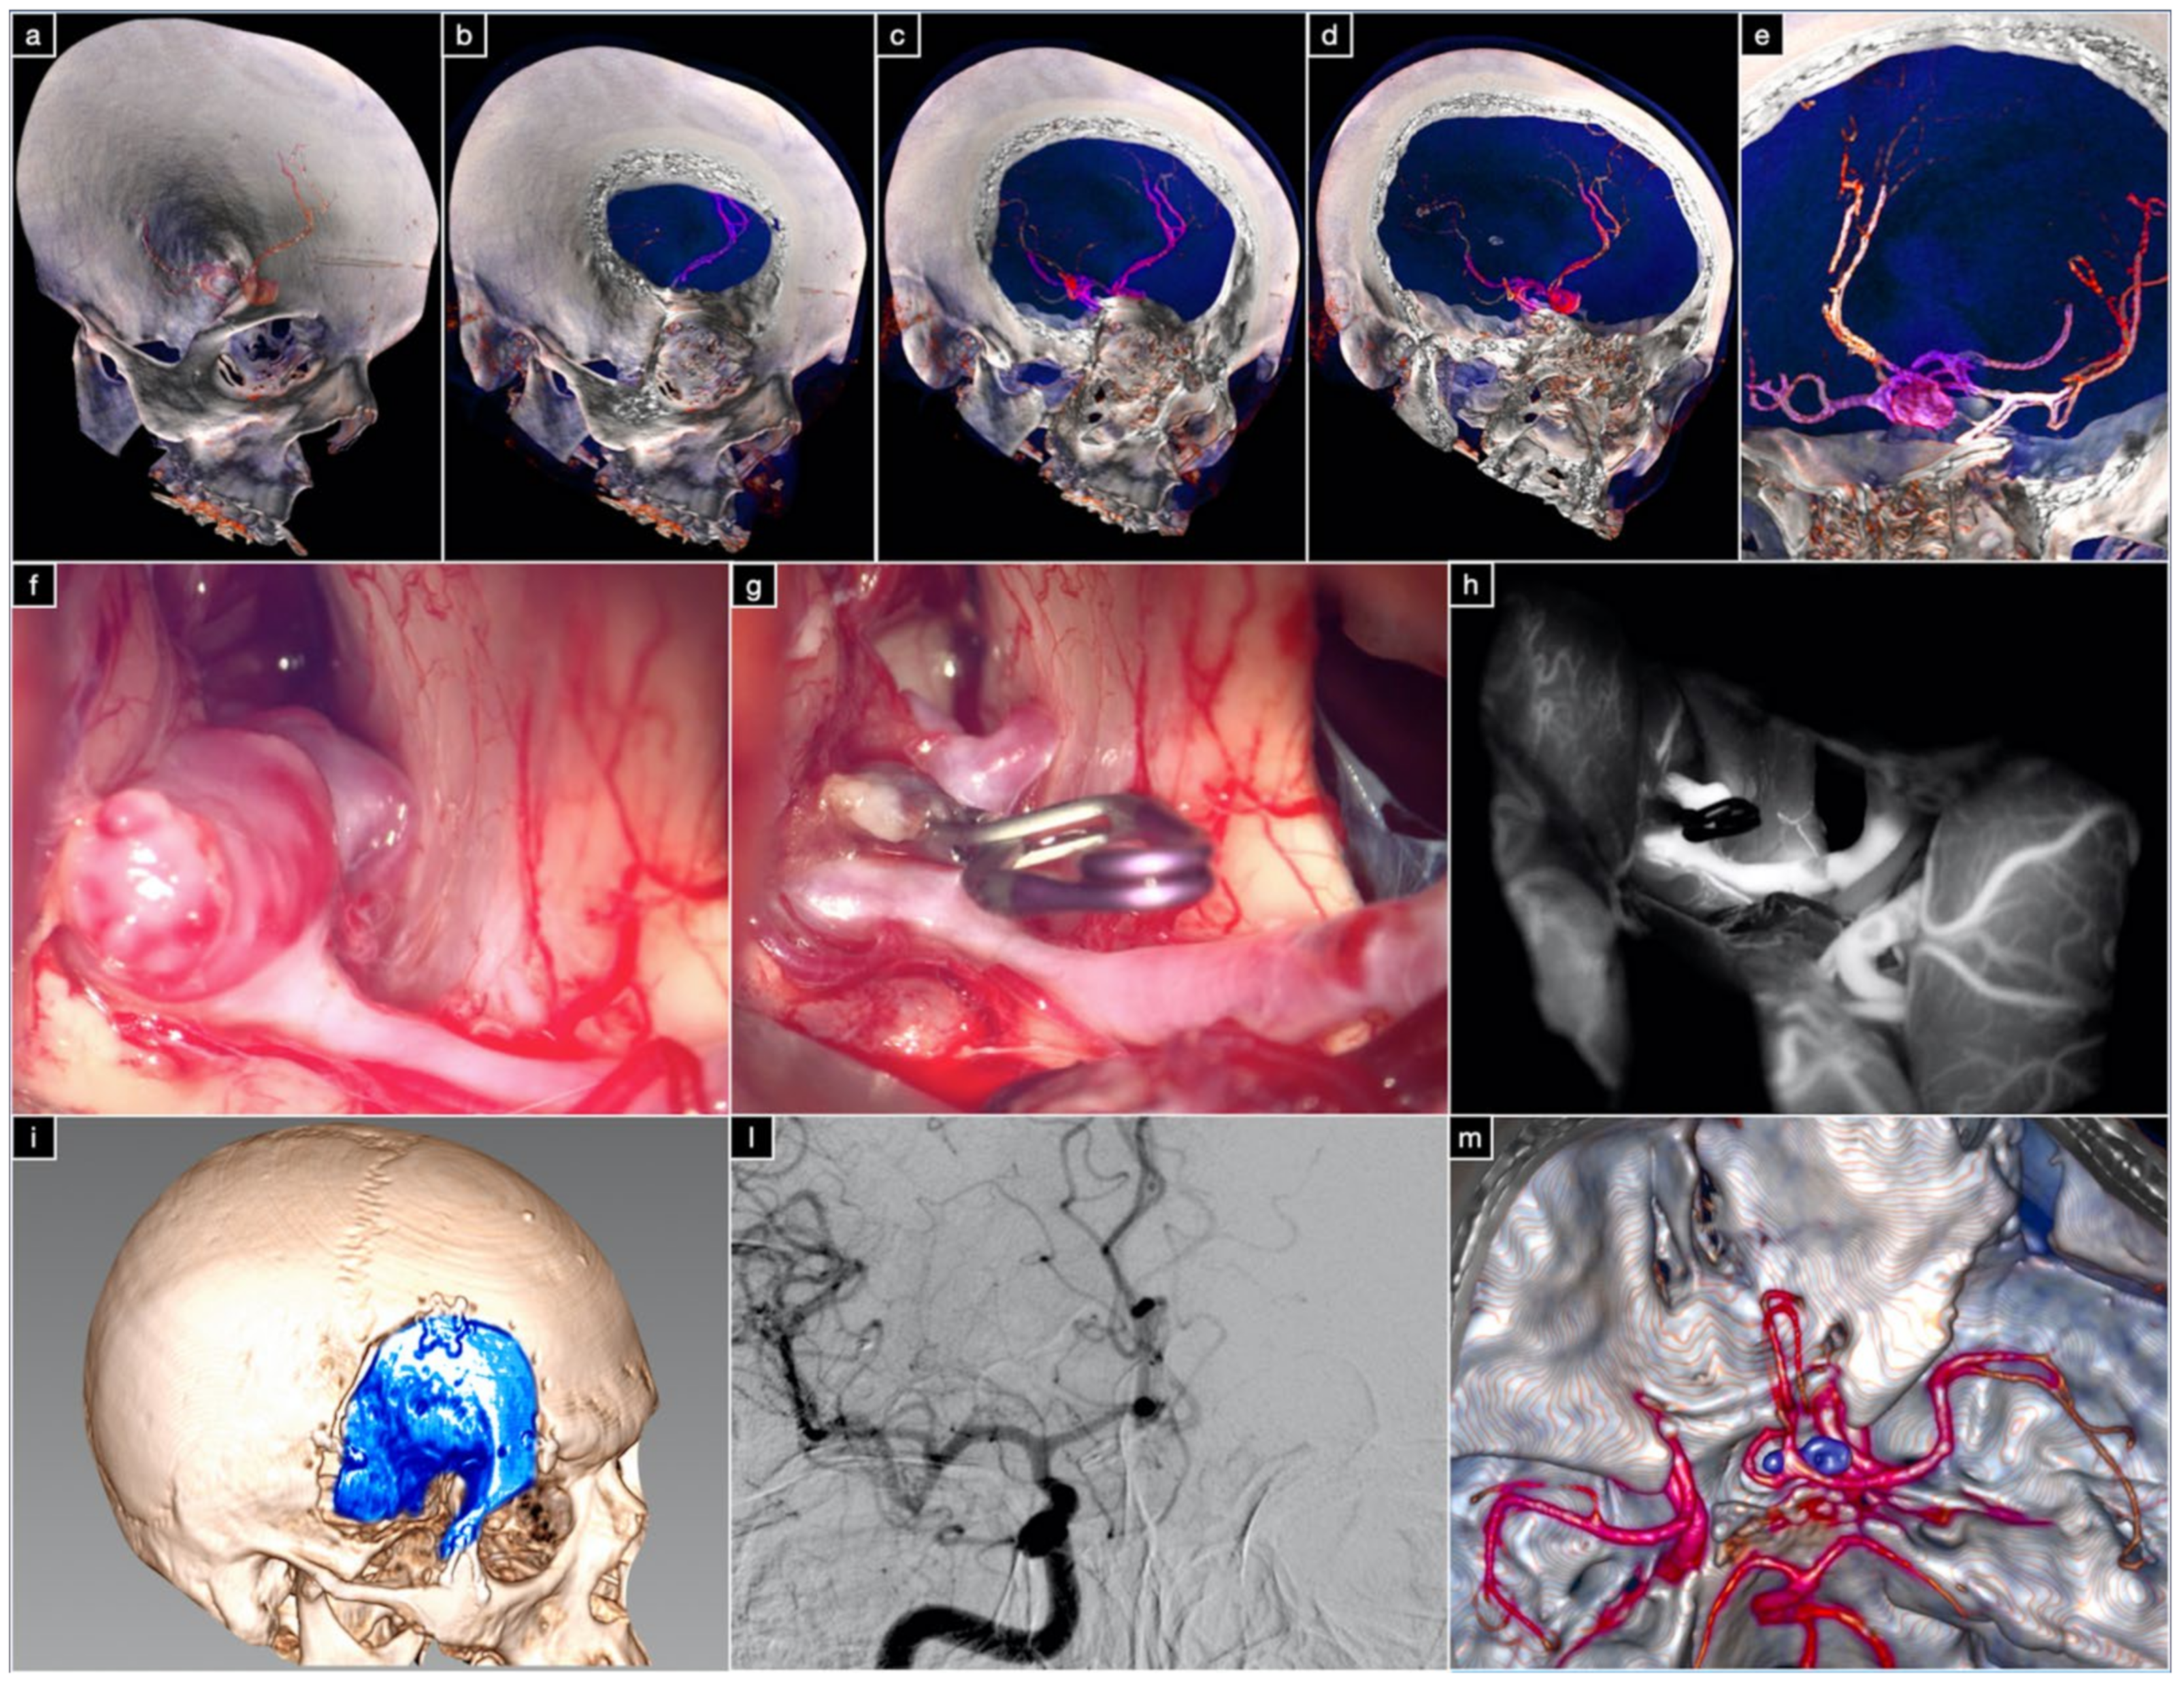

3.3.2. Case 2: Large ACoA Aneurysm